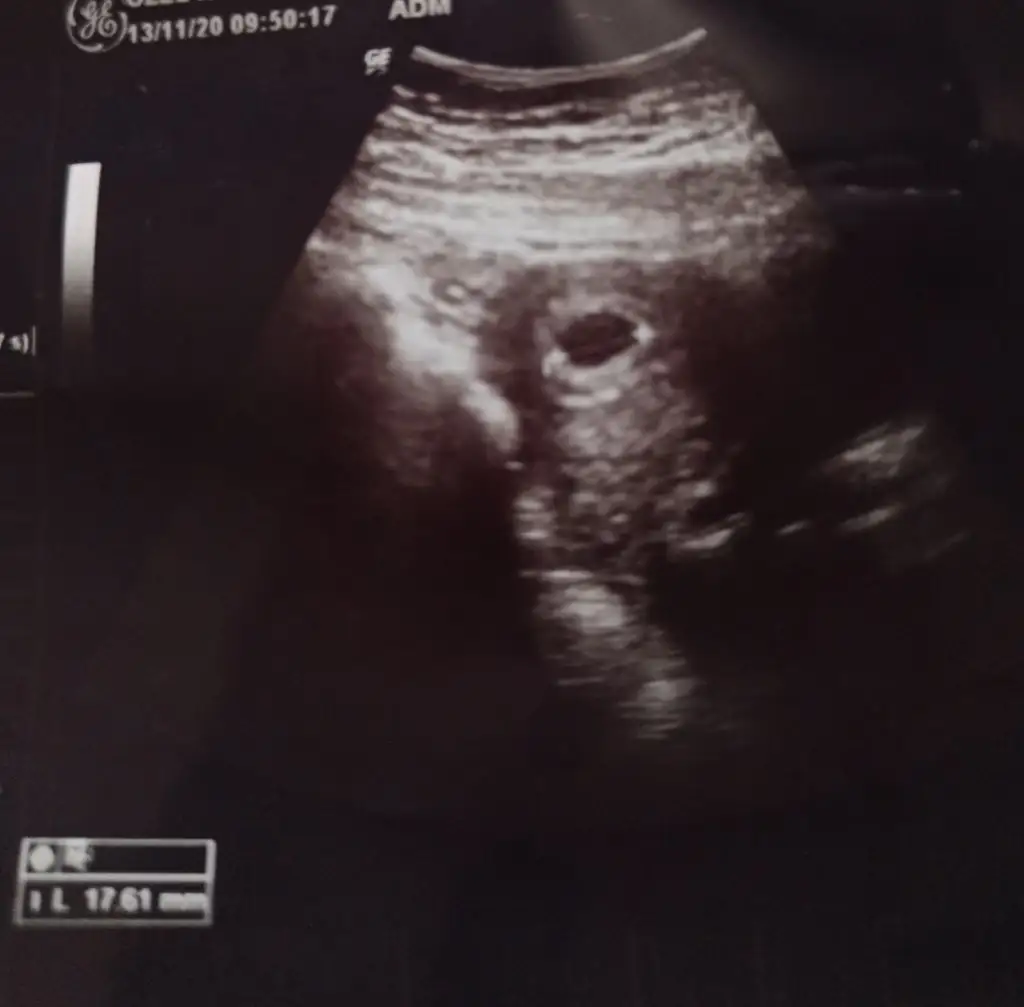

Bu da üstten ultrasonBurda yolk olmalı ama doktorda demiş biraz daha sabret beklemekten başka çare yok Suan inşallah oluşur

Vajinal de çıkardı ama bekle dua etKızlar yuklediklerim vajinal ultrason du